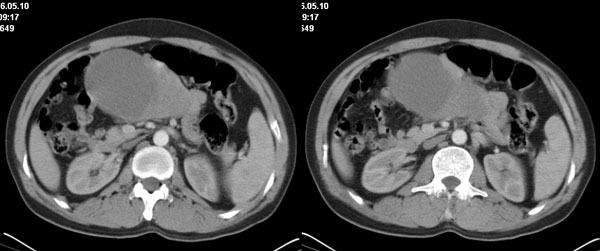

李**,男,46岁,便血1天入院,慢性贫血貌,腹平、软,剑突下压痛,肠鸣音稍活跃,hb大于1g/l,胃镜:慢性浅表性胃炎,b超:1肝内多发性占位 2腹腔内囊性肿块 ,肝内圆形影平扫ct值42.9,动脉期48.6,静脉期58.2,延迟期62.2

影像学表现:1 腹腔前中部、胰腺前方囊实性病灶(个人认为确定有否实性成分存在这是关键,涉及到鉴别诊断,如果是口服阳性造影剂则可明确左侧是不是小肠了),囊性部分囊壁不均,实性部分有强化,与小肠关系较密切,局部小肠受推移;与胰头、胃后壁均有脂肪间隙存在;2 胰腺无异常改变,胰周无渗出;3肝后段包膜下2个小圆形低密度灶,从图像和楼主提供的ct值来看有轻度强化,灶周无片状强化,不似单纯囊肿及肝癌、炎性病变表现;4 腹膜后及腹腔内无淋巴结肿大。

胰腺边界清晰,胰周筋膜不厚,胰周脂肪密度无明显增高;其前方囊实性病灶,边界清晰,增强后实性部分轻度强化;肝内多发边界清晰低密度影,增强后无明显强化(平扫ct值42.9,动脉期48.6,静脉期58.2,延迟期62.2)。

原因:胰头前方,前上腹部巨大囊实性肿物,与小肠关系密切,与胰头及胃壁之间脂肪间隙存在,囊壁不均匀,部分强化,占位效应明显,小肠上段扩张,十二指肠及胃腔内大量食物存留,说明上消化道有部分梗阻。因此,考虑来源于肠道的肿瘤。再结合其病史及肝内改变,这样考虑更有道理。